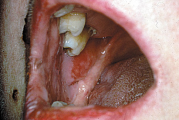

– Üle poolte haigusjuhtudest algab suus esinevate, kiiresti purunevate villidega. Villid on läbipaistvad ja pehmed ning piirduvad algul, mõne kuu jooksul, ainult ühe piirkonnaga ja levivad seejärel üle kogu naha. Tervena näiv nahk villi ümber irdub sõrmega vajutades (Nikolsky sümptom). Loe edasi »